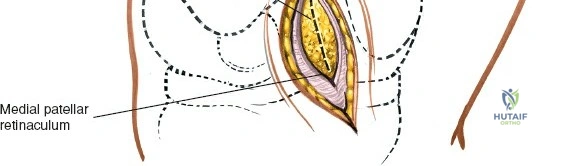

Open Medial Meniscectomy – The Specific Approach

The open medial meniscectomy, once the standard, is now reserved for scenarios where arthroscopy is unavailable, technically infeasible (e.g., severe arthrofibrosis, large foreign bodies, or specific revision surgeries), or for very large, difficult-to-manage loose bodies. The seed content heavily focuses on this approach.

Landmarks and Incision:

- Landmarks: Palpate the medial joint line, medial epicondyle of the femur, and medial tibial plateau. The saphenous vein and nerve courses superficial and posterior to the medial femoral condyle, requiring careful attention.

- Incision Options (as per seed content):

- Transverse Skin Incision: "over the joint line; although this limits the view of the knee, it provides better access to the meniscus itself." This may be suitable for isolated, easily accessible mid-body tears.

- Longitudinal or Oblique Incisions: "offer a better view of such other intra-articular structures as the cruciate ligaments." These incisions provide broader exposure and are generally preferred for better visualization of the entire meniscus and other intra-articular structures. A paramedial, slightly curved longitudinal incision, approximately 5-7 cm in length, centered over the joint line, is a common choice. It extends from just above the joint line distally to just below.

- The choice of incision depends on surgeon preference and the specific pathology being addressed.

Dissection:

- Skin and Subcutaneous Tissue: Incise the skin and subcutaneous tissue. Meticulous hemostasis is maintained.

- Saphenous Nerve and Vein: Careful dissection is paramount to identify and protect the infrapatellar branch of the saphenous nerve and the greater saphenous vein, which lie within the subcutaneous fat layer. Retract them carefully.

- Deep Fascia: Incise the deep fascia.

- Joint Capsule: The approach typically involves either a medial parapatellar arthrotomy, splitting the fibers of the vastus medialis obliquus (VMO) longitudinally, or a direct incision of the medial capsule over the joint line, medial to the patellar tendon. For direct access to the medial meniscus, a paramedial capsular incision along the medial border of the patella and extending distally can be made.